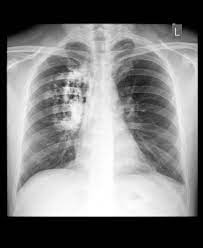

After patient is suspected of lung cancer, the patient may be needed to be investigated for it. The possible investigations may include complete blood counts, inflammatory markets, imaging studies like chest x ray, contrast or non contrast CT scan of chest, bronchoscopy.